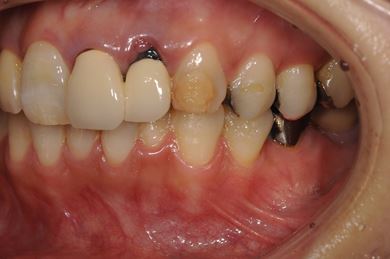

インプラントの症例写真 IMPLANT

骨再生インプラント治療+セラミック治療

| カテゴリー | 【インプラント治療】【セラミック治療】 | ||||||||||||||||||||||||||||||||

| 性別/年齢 | 女性 / 48歳 | ||||||||||||||||||||||||||||||||

| 主訴 | 他の歯科で、前歯の差し歯が折れたところにインプラントをすすめられているので、費用や期間など知りたい。 | ||||||||||||||||||||||||||||||||

| 治療方針 | 骨再生法により、インプラント治療を可能にする。 | ||||||||||||||||||||||||||||||||

| 治療内容 | インプラント1本、メタルボンドセラミッククラウン2本、GBR | ||||||||||||||||||||||||||||||||

| 総治療費 | 618,660円 | ||||||||||||||||||||||||||||||||

| 治療期間 | 9ヶ月 |